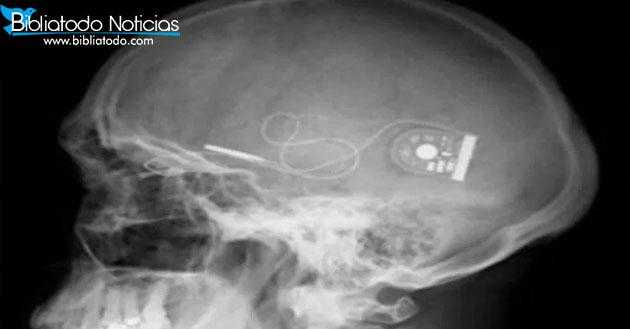

«PROFÉTICO Y APOCALÍPTICO»Se implantan microchips en cerebros, para cambiar el comportamiento de la personas.

Los microchips implantados en los cráneos de las personas están siendo desarrollados por atacantes financiados por la división de investigación Militar Darpa.

Estos implantes usarán pulsos electrónicos para alterar los químicos en el cerebro de las personas en un proceso llamado “estimulación cerebral profunda“. Esto cambiará el estado de ánimo de la gente y se cree que puede tratar la enfermedad mental y proporcionar terapia.

La inteligencia artificial en los implantes de microchip detectará y estudiará el cerebro para saber qué pulsos enviar, descrito por los científicos como una “ventana al cerebro”. “LA DIVISIÓN DE INVESTIGACIÓN DARPA” ha entregado el efectivo a los equipos de la Universidad de California y del Hospital General de Massachusetts.